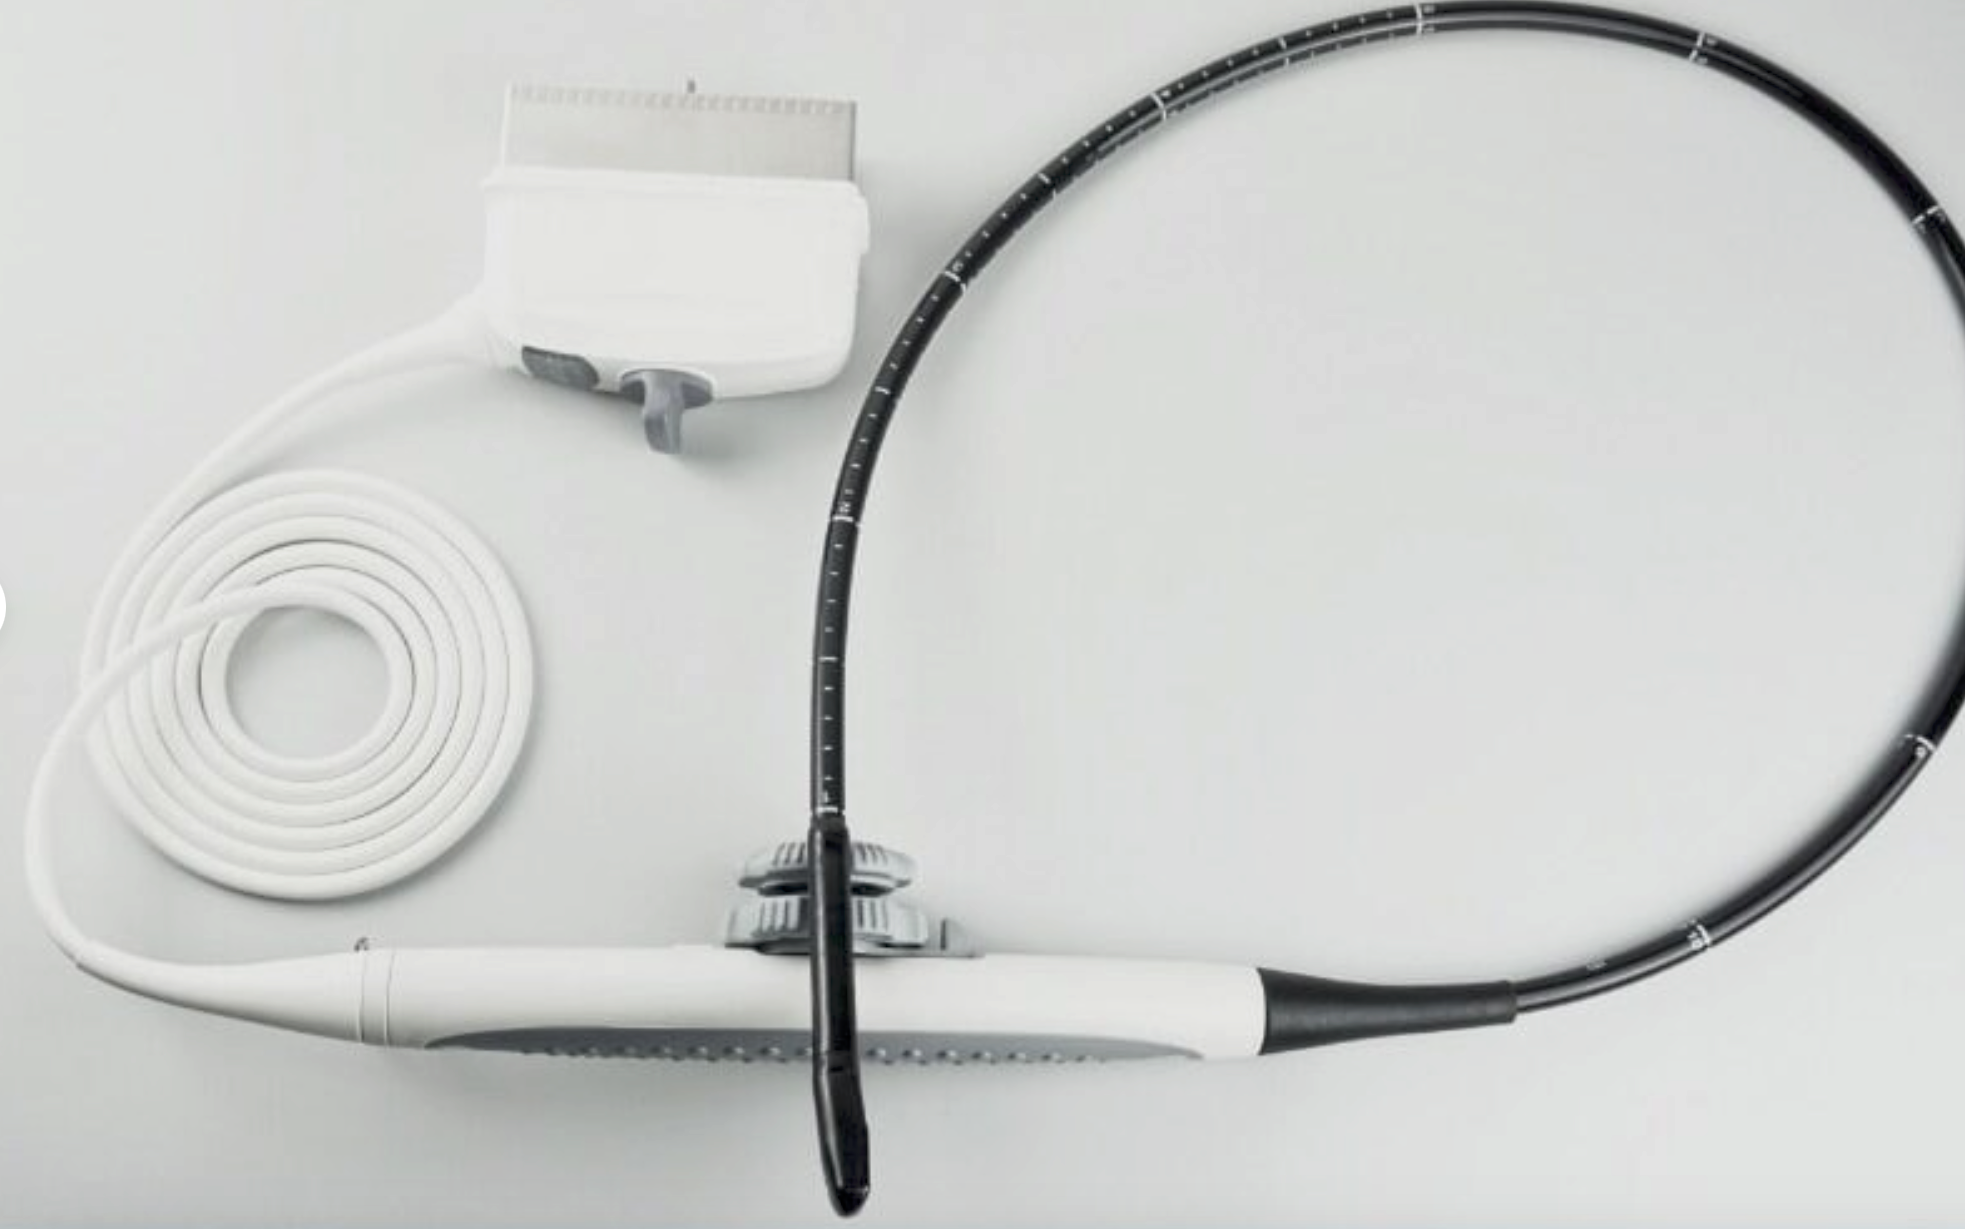

One of the standout features of the TFT LCD Digital Laptop Linear Array Ultrasound Scanner is its linear array probe. This probe is known for its high-frequency linear transducer, which is ideal for scanning small and superficial structures like tendons, arteries, and veins, so it offers precise imaging capabilities. The linear array also supports a range of applications such as musculoskeletal, emergency medicine, and vascular imaging.

Versatility is another key advantage of this ultrasound scanner. It supports a variety of probes that allow for different types of examinations. In particular, the cavity probe included with this machine is useful for gynecological and obstetric purposes. Because this adds another layer of functionality to the device, healthcare providers can deliver comprehensive care using a single machine. With multiple probe options, you can seamlessly switch from one type of imaging to another without missing a beat.